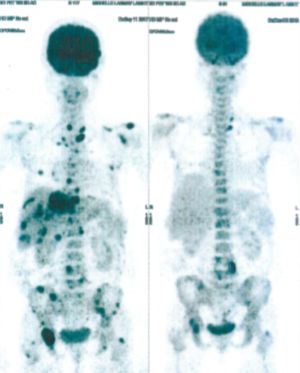

CASE NO: 4 (PROSTATE CANCER)

A middle-aged man with castration resistant prostate cancer and massive bone metastases, failed all currently available cancer treatment, including with the new and expensive drug XTANDI. After a few treatment, most of the bone metastases went into remission, and the remaining ones are less active. Treatment will continue. Cases no: 3 and 4 show that terminal prostate cancer today can be cured with our new cancer treatment.

CASE NO: 5 (BREAST CANCER)

A middle-aged woman with breast cancer that has spread to the anterior chest wall, and numerous chemotherapy could not stop the spread of cancer. After a few treatment, almost all the cancer went into remission. About 6 months later, she is still in remission.

CASE NO: 6 (BREAST CANCER)

A middle-aged women treated for breast cancer now presents with massive liver metastases and a few bone metastases. She refused conventional chemotherapy and came to see us. After just 2 treatment, most of the cancer went into remission and those remaining are less active. Treatment will continue until complete remission.